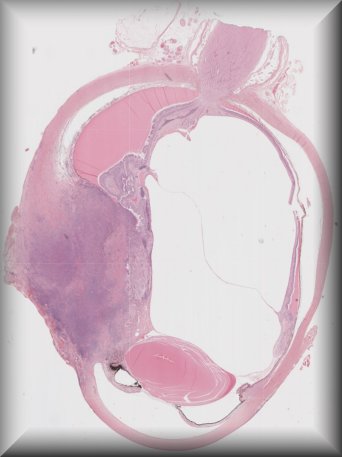

Martina Herwig-Carl (Bonn): 57 year old woman with a blind painful eye and history of intrvitreal bevacizumab injections, tumour biopsy and brachytherapy for uveeal melanoma followed by several proceedures for high intraocular pressure resulting finally in enucleation. |